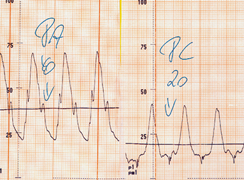

| Abb. 6 |

| Drücke in Pulmonalarterie (PA) und des PC-Drucks (PC). Beachten Sie den stark erhöhten Druck in der Lungenschlagader (links, 45 mm Hg) und den normalen (niedrigen) PC-Druck (rechts) |

Im Normalfall sind der Lungenarterien- und der PC-Druck gleichermaßen jeweils niedrig und damit normal. In diesem Fall sind Herz und Lungengefäße gesund.

Sind beide Drücke erhöht handelt es sich (s.o.) um eine Herzschwäche.

Ist der PC-Druck hingegen normal, der Druck in der Lungenschlagader aber erhöht (Abb. 6) weiß man, daß es eine Behinderung des Blutflusses zwischen dem linken Vorhof (repräsentiert durch den PC-Druck) und der Lungenschlagader gibt.

In diesem Fall kann man davon ausgehen kann, daß diese feinsten Lungengefäße, in denen auch der Austausch von Sauerstoff und Kohlendioxyd stattfindet, z.B. im Rahmen einer Lungenkrankheit erkrankt sind. Die Ursache hierfür muß man nun mit weiteren Untersuchungen (Lungenuntersuchungen evtl. incl. Gewebeentnahme aus dem Lungengewebe) abklären.